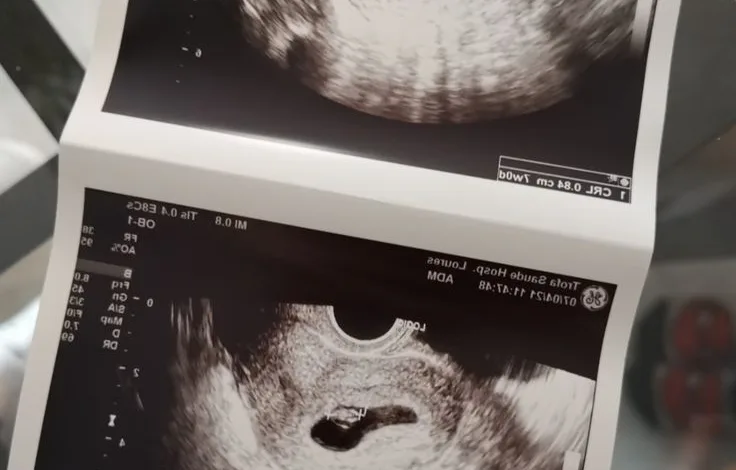

La norma busca que cualquier persona en edad fértil reciba una valoración completa antes de un posible embarazo, con el fin de cuidar su salud y prevenir futuras complicaciones tanto como para la madre o el bebé.

Una adecuada atención antes del embarazo reduce riesgos, previene complicaciones graves y contribuye a proteger la vida y la salud de las mujeres, las personas gestantes y los bebés. Además, fortalece la autonomía reproductiva al ofrecer información clara y acompañamiento oportuno.